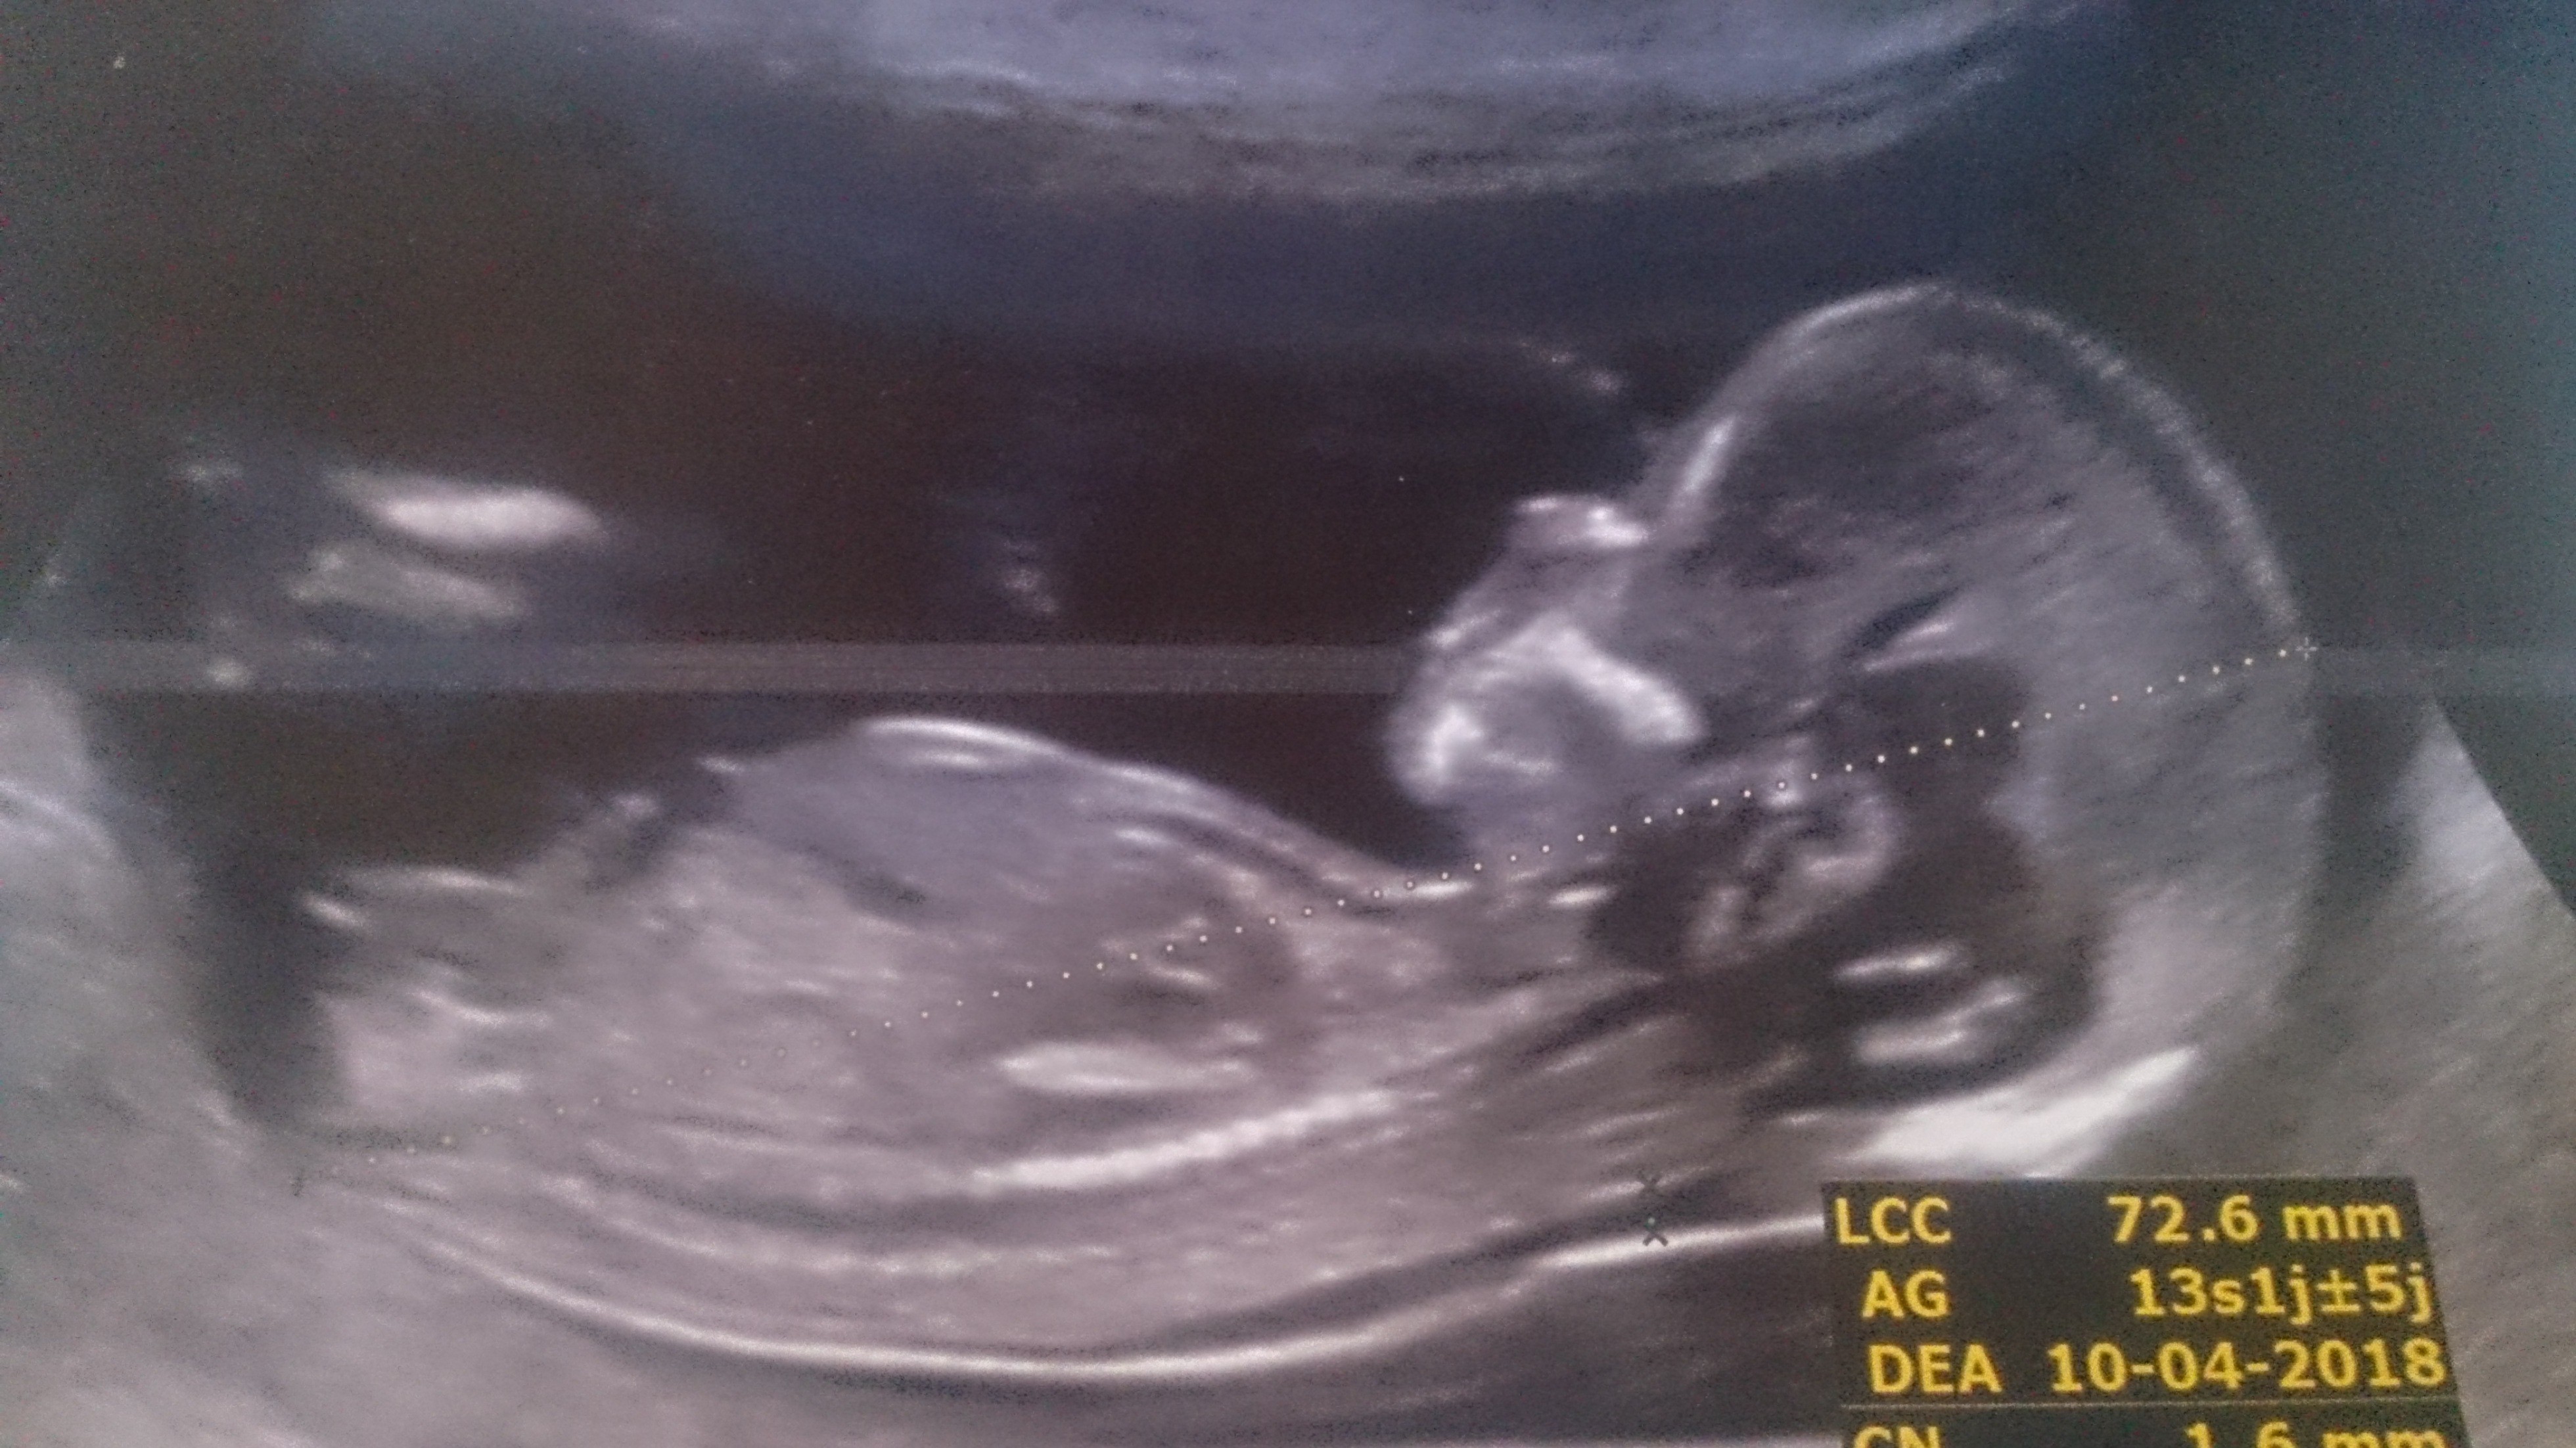

A partir de la 14e ou 15e semaine de grossesse, le ou la gynécologue est en mesure de reconnaître distinctement le sexe du bébé à l'aide d'une échographie Les organes génitaux seront alors visibles sur l'écranQue des histoires de grandsmères et des mythes étranges, mais de quoi passer le temps avant le grand jour!Actuellement il ne faut pas déterminer le sexe fœtal à partir du tubercule génital avant 12 SA car le taux d'erreur est de 40 % et donc ne dépasse que de peu l'effet du hasard l'aspect est dit féminin quand le le tubercule génital part vers le bas et horizontalement l'aspect est dit masculin quand le tubercule génital part en avant et

Ce test peut être demandé quand il y a un risque de certaines maladies génétiques touchant un sexe ou l'autre", précise le gynécologue Quand savoir le sexe de son bébé ?Selon la « nub theory » ou méthode du bourgeon génital, on peut, dès 12 semaines d'aménorrhée environ, avoir une idée du sexe de bébé en étudiant l'angle entre le bourgeon et la colonne vertébrale Chez un garçon, le bourgeon forme un angle d'approximativement 30 degrés avec la colonne vertébraleLe 05h52 Lecture en 3 min L'annonce du sexe du bébé se fait lors de la seconde échographie, entre la e et la 22e semaine de grossesse Mais tout dépend de la façon dont les organes génitaux se développent et du bon vouloir de bébé qui accepte, ou non, ce jourlà de dévoiler son sexe Sexe de bébé rien de

Il y a à peine quelques années, l'échographie était le seul procédé offert aux femmes enceintes afin de connaitre le sexe de l'enfant qu'elles portaient Ainsi, la majorité des futures mères attendaient jusqu'à la moitié de leur grossesse pour réaliser une échographie qui confirmerait le sexe du bébéIl est possible d'avoir une indication sur le sexe de votre enfant lors de votre échographie du premier trimestre en observant l'aspect du tubercule génital du fœtus Cette méthode, dite du bourgeon génital donne de bons résultats, en particulier pour les échographies réalisées à partir de 11 semaines de grossesse (13 semaines dCette façon de faire estelle fiable ?

Avant la 14e semaine de grossesse, il existe d'autres méthodes que l'échographie pour identifier le sexe du fœtus A l'aide du dépistage prénatal (p ex la choriocentèse), les gynécologues peuvent savoir dès la 10e ou 11e semaine si la future maman est enceinte d'une fille ou d'un garçonIl est effectivement possible de voir le bourgeon sexuel (et non le sexe réellement) à l'échographie des 12 semaines, et en fonction de sa position de donner une présomption de sexe Mais des erreurs sont possibles Néanmoins ce n'est qu'à l'échographie des 22 semaines qu'on voit vraiment le sexe et que l'on peut être certainEt voilà toutes nos félicitations vous êtes enceinte Maintenant vous aimeriez bien savoir si bébé est une fille ou un garçon, pour commencer a choisir le prénom, la décoration, et aussi faire passer le temps en attendant son arrivée Le plus simple et le plus certain reste l'échographie de morphologie pour connaitre le sexe de bébé

Plusieurs études scientifique ont évalué son taux de réussite (voir en anglais uniquement, une étude qui date de 1999, une de 06 et une de 12) La conclusion principale est que la méthode du bourgeon génital donne de bons résultats pour les échographies réalisées à partir de 11 semaines d'aménorrhées (9 semaines de grossesse) et pourLe moment auquel est pratiqué l'échographie a son importance En fonction du stade de la grossesse, le spécialiste ne sera pas à la recherche des mêmes élémentsLe clan du oui Comme la majorité des gens, vous avez tellement hâte à la e semaine de grossesse pour enfin connaître le sexe de ce petit être qui grandit dans votre ventre!